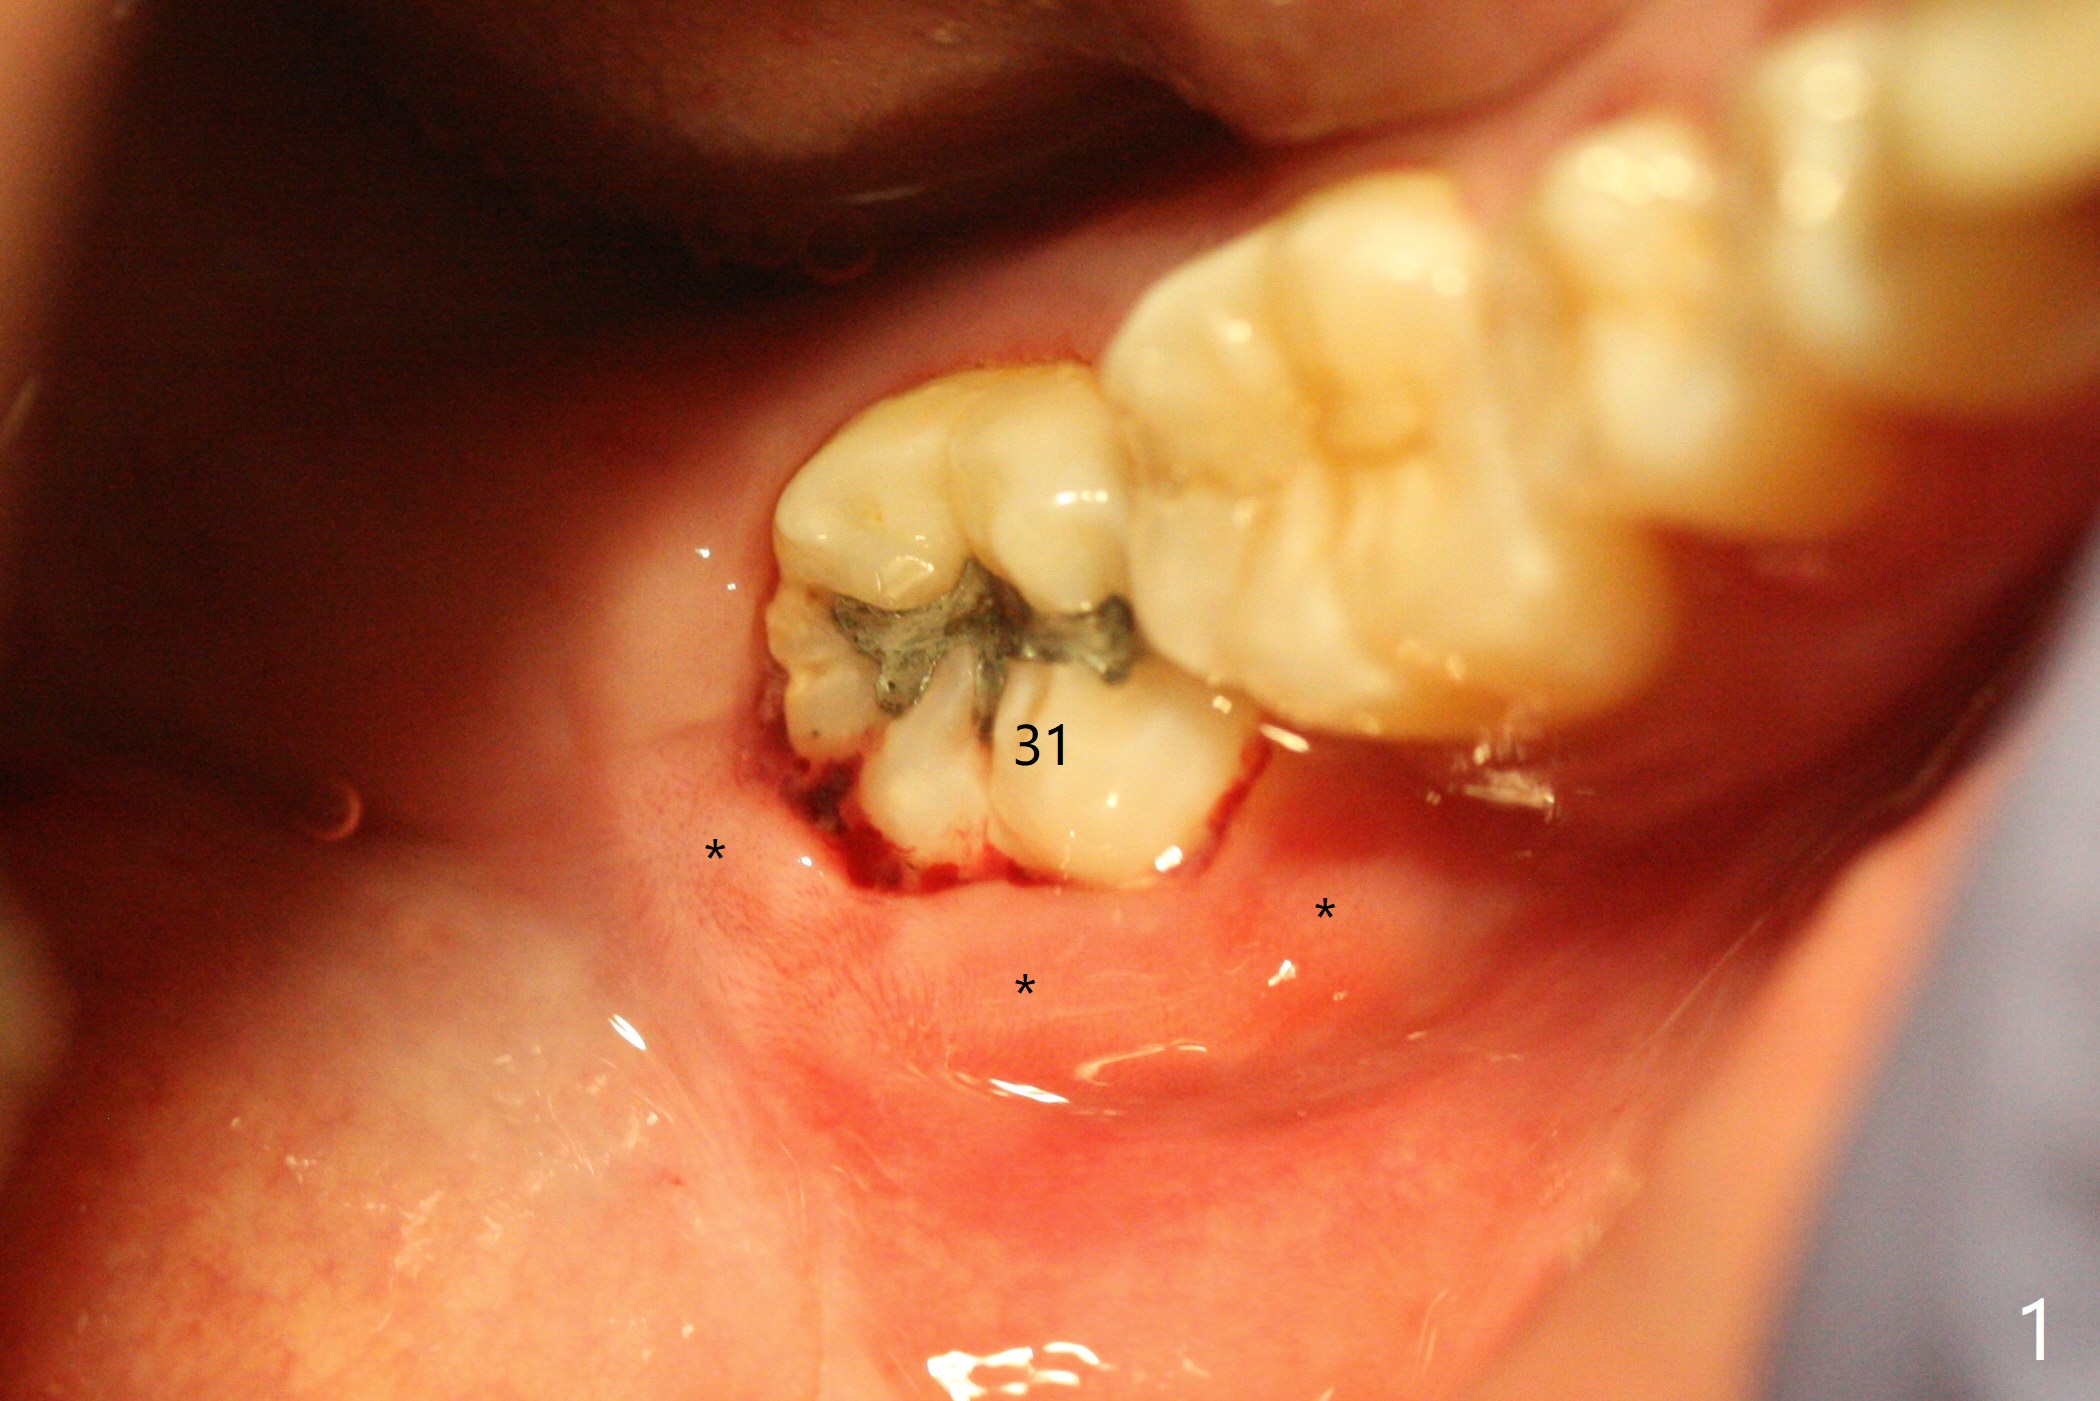

A 22-year-old man with poor oral hygiene requests extraction of the lower right 3rd molar. The buccal gingiva of the 2nd molar is erythematous and edematous (Fig.1 *). There is tenderness between #31 and 32 with severe bone loss (Fig.2 *). After extraction and debridement (Fig.3), Osteogen plug is inserted into radicular portion of the socket (Fig.4 white outline), while allograft is placed coronally (Fig.5, 7), covered by Collagen plug (Fig.6) before suturing. The bone fills the whole socket 1 year postop (Fig.8); there is no root surface exposure at #31. The bone fills the whole socket of #32 one year postop (Fig.8); there is no root surface exposure at #31.